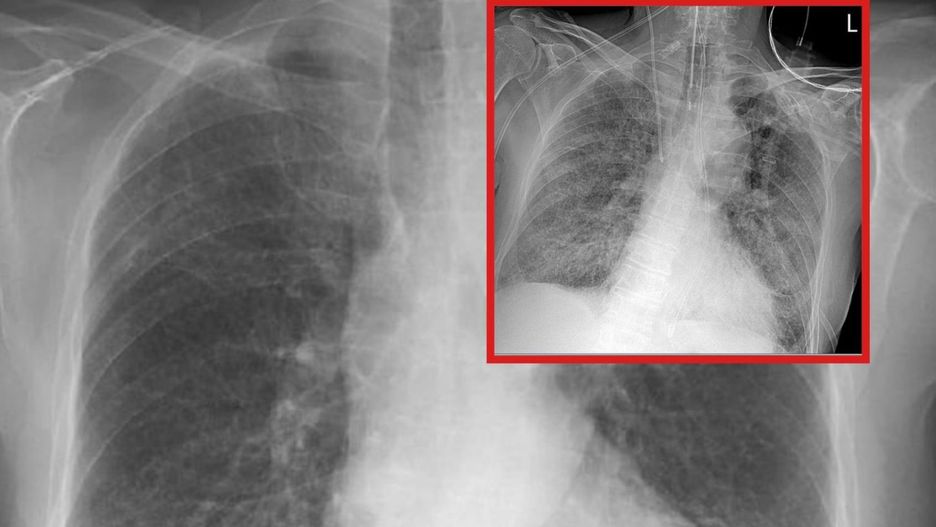

Lekarze od miesięcy przekonują, że koronawirus powoduje w płucach chorego ogromne spustoszenia. By uciąć spekulacje, publikują na to dowody - zdjęcia RTG, na których widać zmiany wywołane przez SARS-CoV-2. Tak też zrobił Tomasz Rezygent, lekarz w trakcie specjalizacji z chorób wewnętrznych, publikując w sieci 2 fotografie, na których widać stan płuc pacjenta z COVID-19.

Obraz płuc, na którym widać zapalenie płucObraz płuc, na którym widać zapalenie płuc

Rezydent opublikował dwie fotografie RTG, które były wykonane u jednego chorego z pozytywnym wynikiem na koronawirusa. "Pierwsze RTG wykonano przy przyjęciu do szpitala, u pacjenta dodatniego z osłabieniem i gorączką, jeszcze bez duszności. Drugie wykonano u tego samego chorego po 7 dniach hospitalizacji, już w skrajnej niewydolności oddechowej wymagającej respiratoroterapii" - opisuje lekarz.

Obraz płuc przed wystąpieniem duszności

Obraz płuc przed wystąpieniem duszności © Tomasz-Rezydent

Wyjaśnia, że ciemnie obszary płuca na pierwszym zdjęciu są w większości z niezmienionej jeszcze chorobowo tkanki, natomiast nakrapiane mlecznie płuca są praktycznie w całości zajęte (odpowiadają 80 proc. zajętego miąższu w tomografii komputerowej).